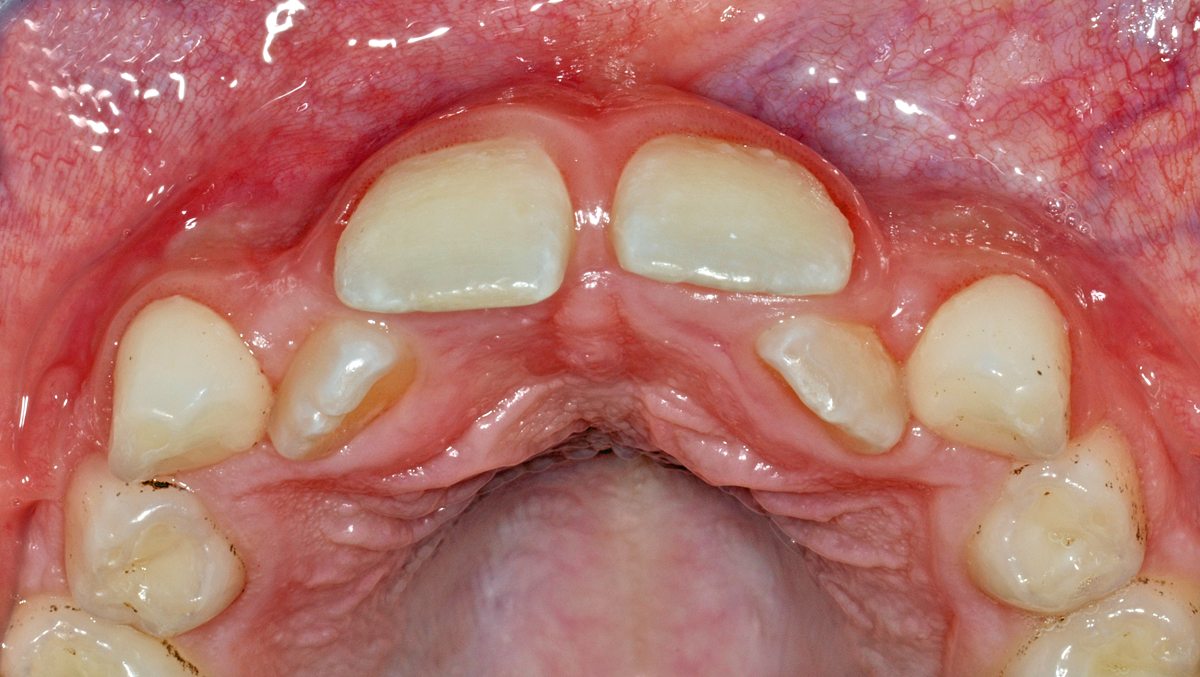

Diese Abweichung ist dadurch bedingt, dass die seitlichen Schneidezähne zu weit auf der Gaumenseite (im zahnärztlichen Vokabular: palatinal) durchgebrochen sind. Nebst der ursprünglichen Lage der Zahnkeime beim Wachstum ist sicher auch die zu knappe Platzsituation (auf dem folgenden Bild gut zu erkennen) mit daran beteiligt.